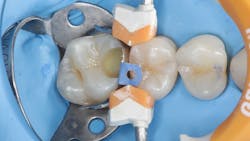

While performing esthetic dentistry, our bonding materials must work as promised to achieve long-term success.2 When manufacturers report bond strengths in the clinical arena, studies are conducted with the rubber dam in place (figures 1 and 2). When etched surfaces are exposed to the oral environment, including expired air while using typical isolation devices, the surfaces are challenged by moisture from numerous sources, causing the adhesive chemistry to be altered. Hence, to achieve the best bond strengths, a well-sealed barrier will help our results, often dramatically.

In addition to optimal bonding, the rubber dam may retract the tissues when placed properly, improving our visualization of finish lines, margins, and adhesive materials. One of dentistry’s rubber dam advocates, Dr. Hunter Brinker (the inventor of the B1-B6 clamps), often said “to see is to know” when referring to the benefits of the rubber dam to improve attention to detail through better visual access. It is interesting to note that when the rubber dam is properly placed, it will not only retract the tongue, lips, and cheeks, but it will also atraumatically retract the gingiva, typically 2–3 mm, and expose areas that could not be visualized by any other nonsurgical means (figures 3–5).